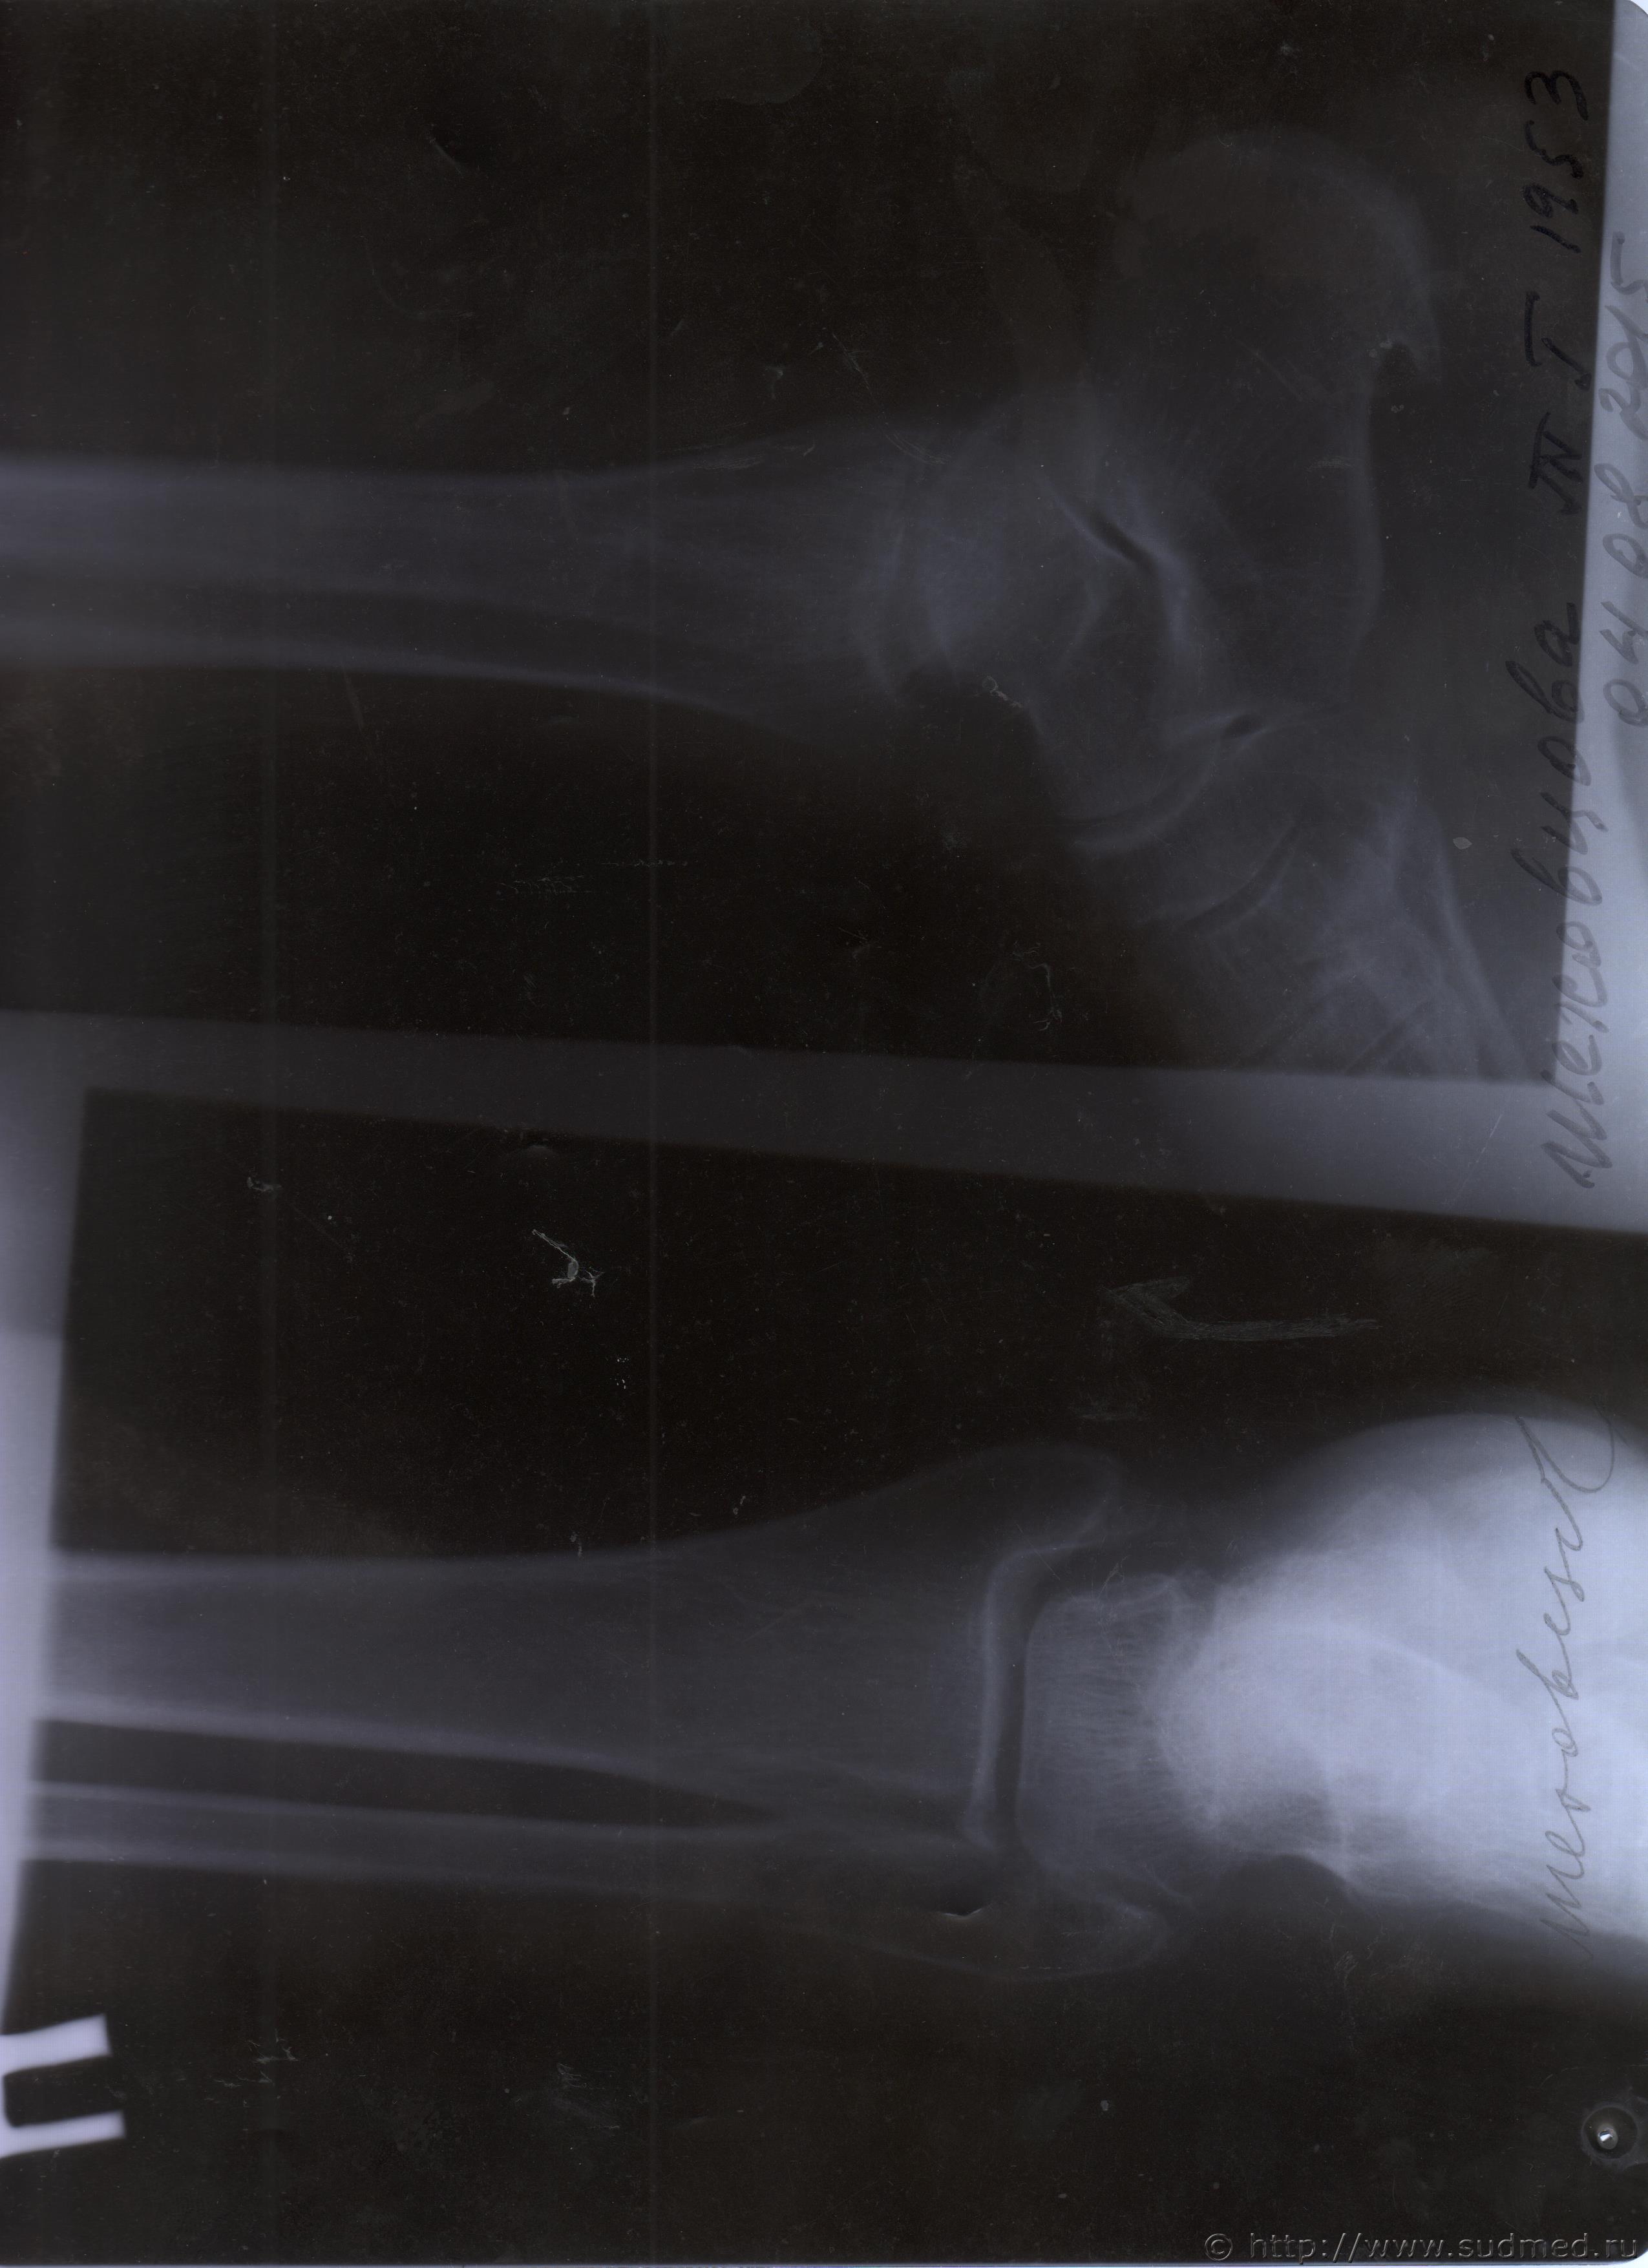

06.07.2015 г. при обращении в горбольницу мне выдали не описанный снимок( все рентгенологи были в отпуске) и справку № 4379 от 06.07.15 г. где диагноз: закрытый 2-х лодыжечный перелом правой голени без смещения. Копию справки прилагаю

За все 12 месяцев, что была на больничном, 8 раз делали снимки травмированной ноги и все заключения именно : «закрытый 2-х лодыжечный перелом правой голени без смещения».

После того, как был поставлен диагноз : «компрессионный перелом L2 позвонка поясничного отдела позвоночника». Амбулаторная мед карта, была украдена из кабинета врача травматолога. При восстановлении мед карты( в марте 2016 г.), врачом травматологом была взята копия справки от 06.07.15 г.из приемного отделения горбольницы. Справка № 4379 ( дубликат), диагноз : «закрытый 2-х лодыжечный перелом правой голени без смещения».

Уважаемые доктора, нужны ли снимки по перелому правой голени? и Заключения по МРТ и КТ.Ранее представляла результаты обследования...Сделала копию снимков по КТ и МРТ( только вот какого качества получились не знаю.)

Посмотрите, пожалуйста

Посмотрите, это снимки за 12 месяцев.

Уважаемая Татьяна! По представленным Вами снимкам ничего сказать нельзя: нет маркировки даты каждого снимка (поэтому, невозможно их сравнивать друг с другом и соотносить с датой травмы), исследование непосредственно пленок гораздо более информативно, чем анализ представленных изображений (детали костной структуры в зоне перелома практически не видны).

Рекомендую проконсультировать все эти снимки у высококвалифицированного рентгенолога. Далее - по ситуации, т.е. в зависимости от его мнения. В любом случае, есть формальные основания для назначения дополнительной экспертизы, т.к., судя по представленному Вами фрагменту заключения эксперта, на экспертизу не были предоставлены все мед.документы с данными о лечении предъявляемой травмы (Вы пишете, что рентгенограммы делались на протяжении 12 месяцев, полагаю, что Вы и врачами наблюдались в течение этого срока, т.е. велась мед.карта).